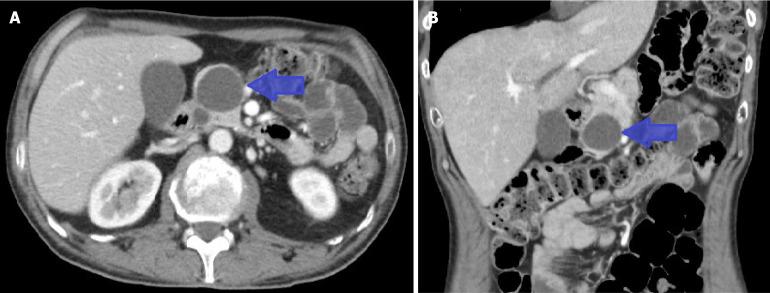

We describe the case of a 50-year-old male recently diagnosed with small-cell lung cancer (SCLC). The patient was admitted to the emergency department with acute abdominal pain and subsequently diagnosed with AP. He was hospitalized under the care of the gastroenterology service. During the etiological workup, metastatic pancreatic lesions were identified on imaging, which had not been observed on the initial cancer staging. Following resolution of the initial episode, oral intake was introduced, but the patient experienced recurrent abdominal pain and laboratory abnormalities consistent with new episodes of AP. This pattern repeated over the following days. After several episodes, and with suspicion of a metastatic origin, the case was discussed in multidisciplinary meeting. In agreement with the patient and given the need to initiate treatment for the primary tumor as well, chemotherapy was started. This treatment successfully alleviated symptoms, allowing dietary progression without complications and discharge from the hospital.

我们描述了一名50岁男性患者,最近被诊断为小细胞肺癌(SCLC)。该患者因急性腹痛入院,随后被诊断为AP。他在胃肠病科的护理下住院。在病因检查过程中,影像学检查发现了转移性胰腺病变,这在最初的癌症分期中未被观察到。初始发作缓解后,开始经口进食,但患者反复出现腹痛和实验室检查异常,与新的AP发作一致。这种情况在接下来的几天里反复出现。经过几次发作,并怀疑有转移起源后,该病例在多学科会议上进行了讨论。经与患者协商并考虑到也需要开始对原发性肿瘤进行治疗,于是开始了化疗。这种治疗成功缓解了症状,使饮食逐步恢复且无并发症,并得以出院。